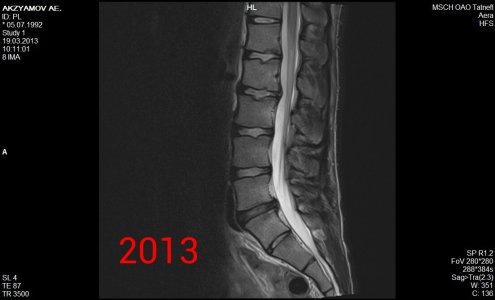

Здравствуйте! Я парень, мне 21 год, рост 190, вес 90, у меня поясничные грыжи l1-l2 1,8 мм, l2-l3 3,5 мм, l5-s1 4,4 мм, беспокоит уже 1,5 года слабость в ногах сначала была боль в левой ноге затем исчезла, и появилась постепенно слабость с внешней стороны квадрицепса до большого пальца ноги, и справа от колена по внешней стороне до большого пальца вниз, больше интересует непостоянность этих симптомов, то есть они могут вообще исчезать на один день и появляться на другой, могут появиться просто когда лежал телевизор смотрел и при этом спина вообще не болит, и в ногах боли тоже нет, невролог проводивший осмотр направлял на вич, гепатит, сифилис все чисто. Если начинаю пить прозерин по 2 таблетки в день все как рукой снимает. Ниже приведены все снимки и заключения имеющиеся на руках.Что это может быть, почему слабость может так быстро исчезать и появляться снова, грыжи то на месте может это что то другое? И еще хотелось бы узнать ваше мнение по поводу записи в заключении 2013 года (Арахноидальная киста в мягких тканях на уровне межостистых отростков L5-S1 7x8-8x2 мм) она не может сдавливать нервы?